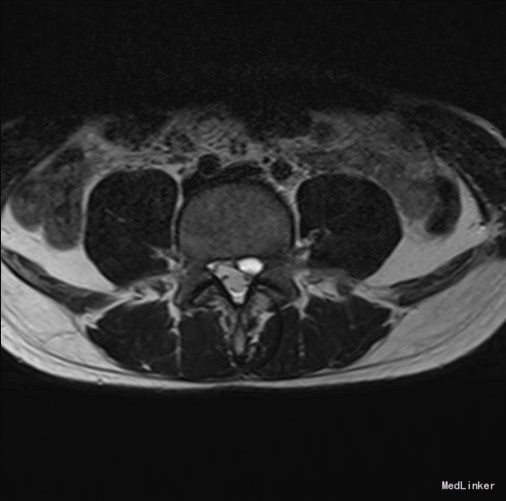

椎管侧隐窝占位1例

主诉 病史

左侧下肢放射痛1月加重2天

查体 辅查

腰椎前屈受限,腰4-5左侧棘突旁压痛,左侧直腿抬高试验小于30°,肌力正常。

诊断 处理

腰椎椎管内占位 腰椎后路开窗减压+椎间融合+内固定术